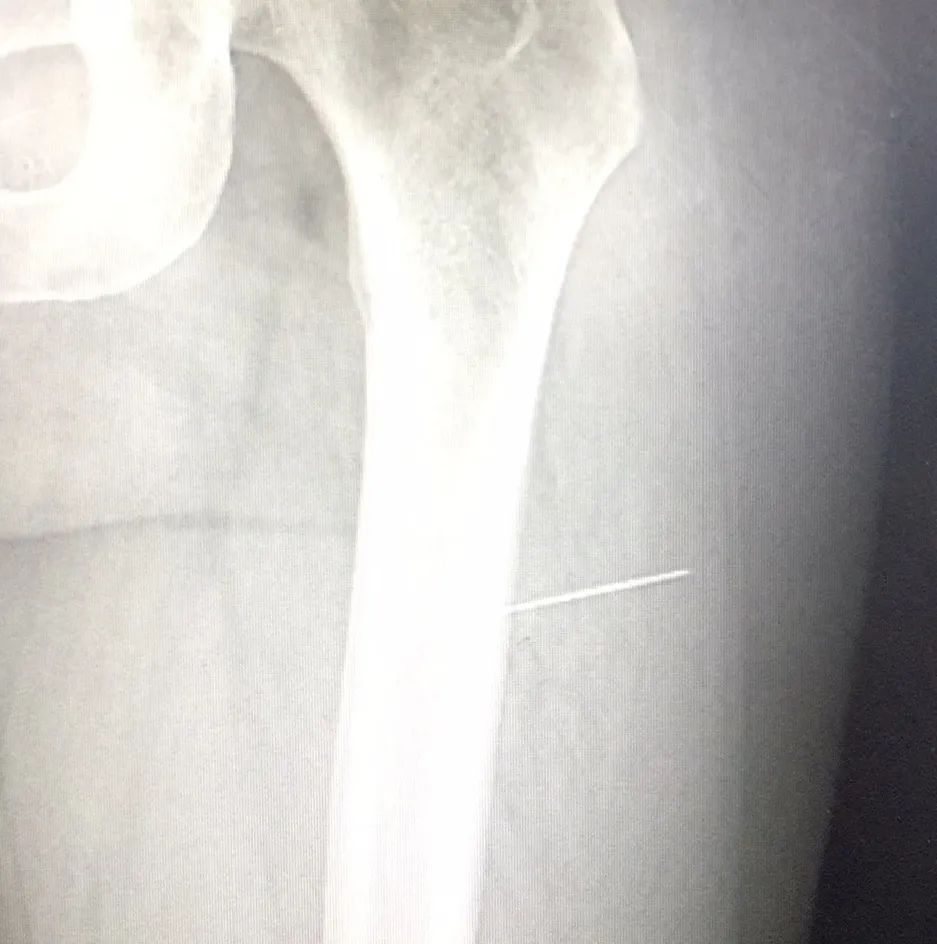

说起来也挺玄乎,邹女士(化名)在十一月初在回家途中不慎撞到了什么,当时只感觉左大腿像被针轻轻刺了一下,没有伤口,也没有出血,邹女士也就没当一回事。可是这才只是开始,随着行走,邹女士只觉得左大腿莫名其妙地开始疼痛,接下来的十几天里,疼痛逐渐加重,休息时才能缓解。邹女士一直想不明白,这腿到底是什么毛病。

百思不得其解的邹女士来到足踝医学科,由于没有外伤史,郑天翔医师建议进行医学影像检查,拍片时发现邹女士的腿部存在金属信号,片子显示,邹女士的左大腿横插着一根针状金属。考虑到年轻的邹女士对创口愈合后美观程度的需求,在向学强医师的配合下,郑天翔医师在邹女士的腿部开了个尽可能小的创口,取出了一根针。